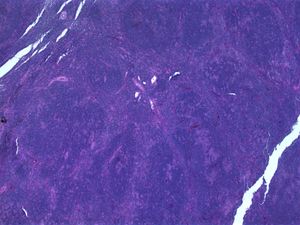

سرطان الغدد الليمفاوية هودجكين، النوع الذي تسود فيه الخلايا الليمفاوية العقدية. لاحظ تكوين العقد الليمفاوية ومناطق التبقيع (صبغة الهيماتوكسيلين والإيوسين)

تظل العديد من الأورام اللمفاوية منخفضة الدرجة بطيئة لسنوات عديدة. وغالبًا ما نتجنب العلاج للمريض الذي لاتظهر عليه أعراض، نكتفي فقط بالانتظار والمتابعة. وذلك لأن الأضرار والمخاطر الناتجة عن العلاج تفوق الفوائد.[32] أما عند ظهور الأعراض فيكون العلاج الإشعاعي أو العلاج الكيميائي هما الاختيار؛ على الرغم من أنها ليست علاج نهائي لسرطان الغدد الليمفاوية، وإنما يمكن أن تخفف الأعراض، لا سيما تضخم العقد اللمفاوية. المرضى الذين يعانون من هذه الأنواع من سرطان الغدد الليمفاوية يمكن أن يعيشوا أعمارًا شبه طبيعية، ولكن بدون شفاء من المرض. هناك دعوات لاستخدام ريتوكسيماب في علاج سرطان الغدد الليمفاوية بدلا من الانتظار والمتابعة تجنبًا للقلق الشديد لدى المرضى.[33]